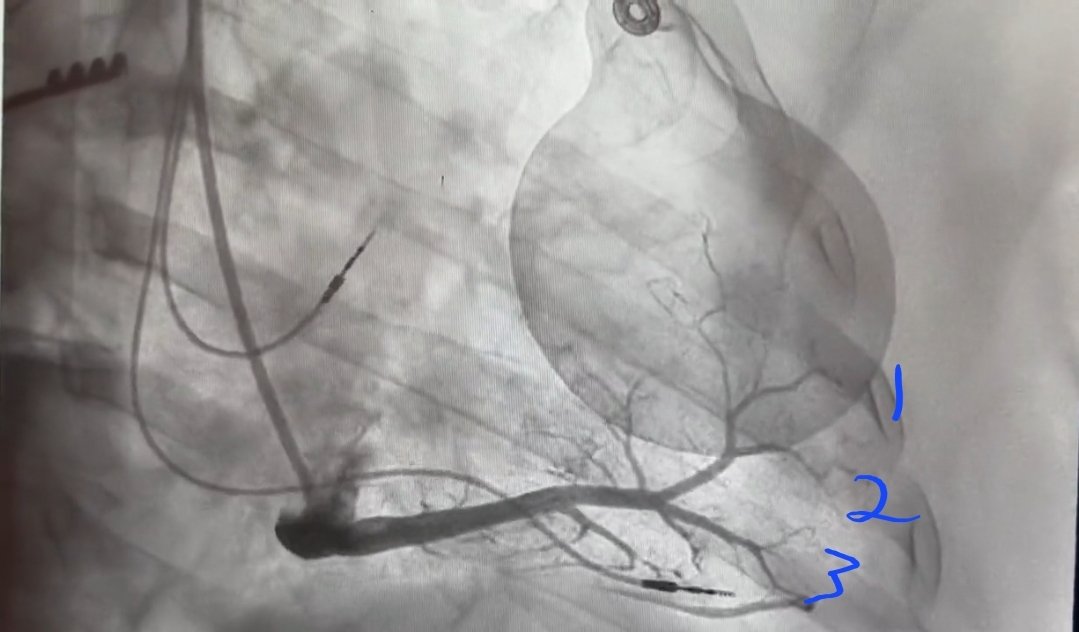

@DrRoderickTung In the advent of wider WACAs with some PFA systems; whats your threshold of finishing a PWI when an isthmus remains? Another area of uncertainty of whats safe to leave.

What’s the obsession with PWI in AF ablation? It may appear “safe & easy” @drjohnm BUT no randomised evidence & there is downside #TWIC Oct 10